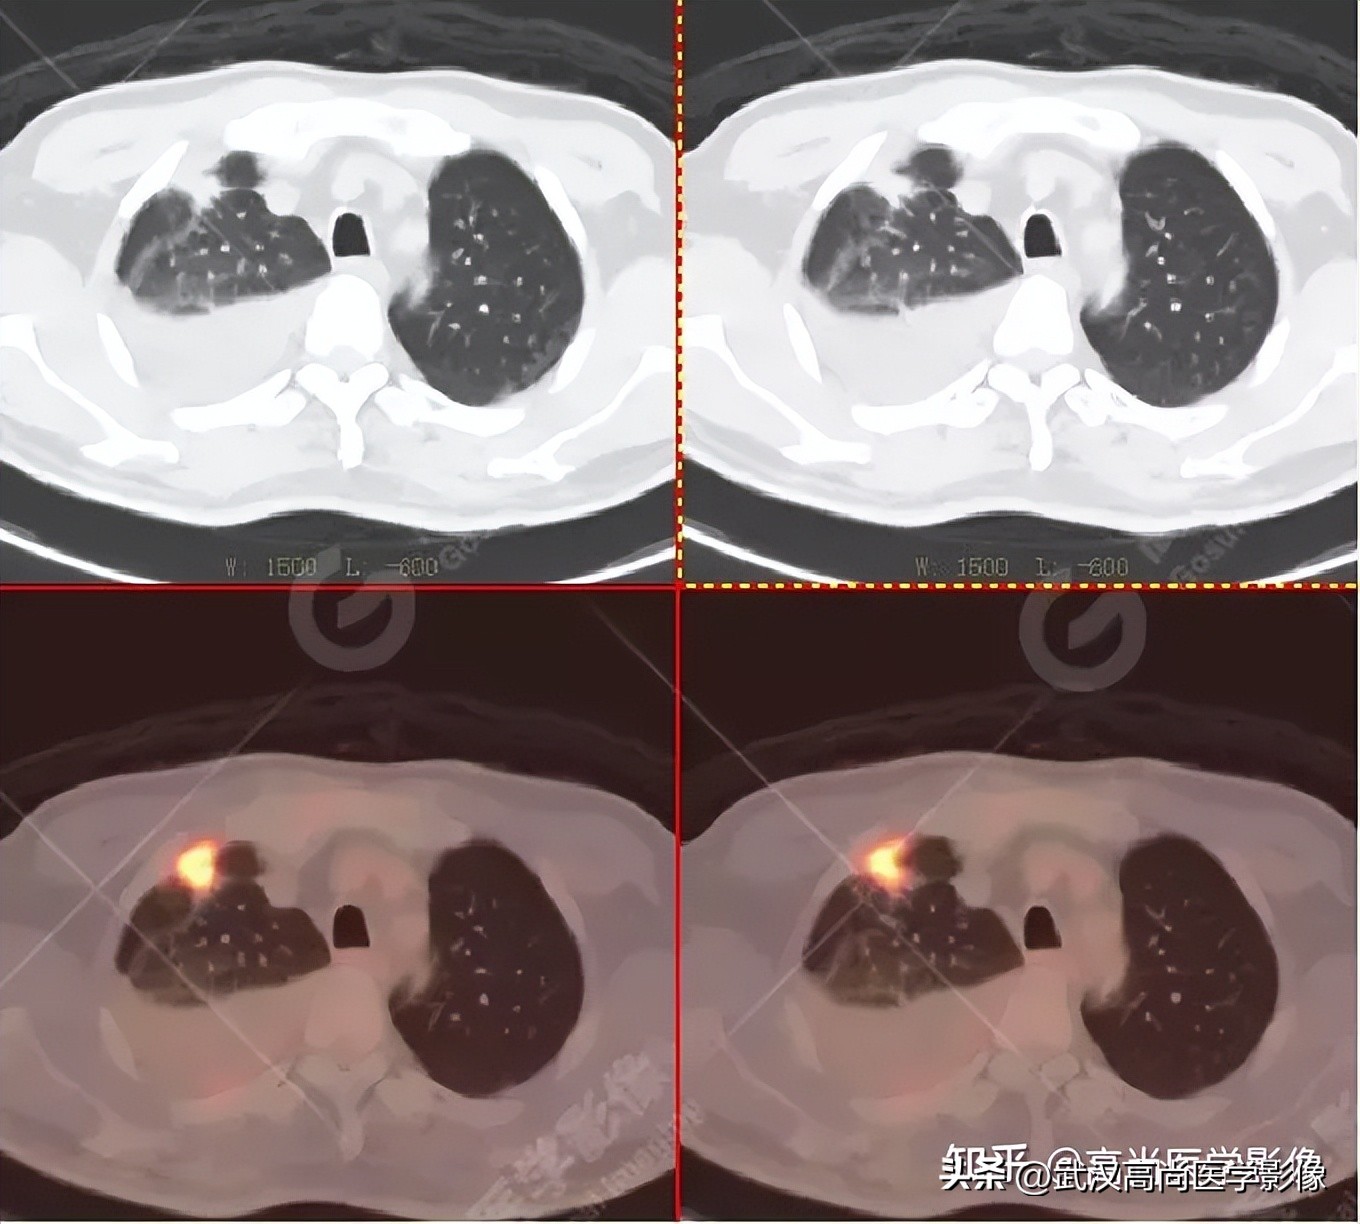

影像表现:

右肺下叶背段见一实性结节,大小约2.0cm×1.6cm×1.8cm,CT值33Hu,FDG高摄取,SUVmax13.0。

恶性CT征象:

病灶边缘分叶、短毛刺,其近端亚段支气管截断,瘤肺界面清楚,病灶远端片絮状阻塞性炎症。

PET/CT诊断结论

右肺下叶背段周围型肺癌,伴多发淋巴结、左侧小脑半球、肝脏、骨多发转移。